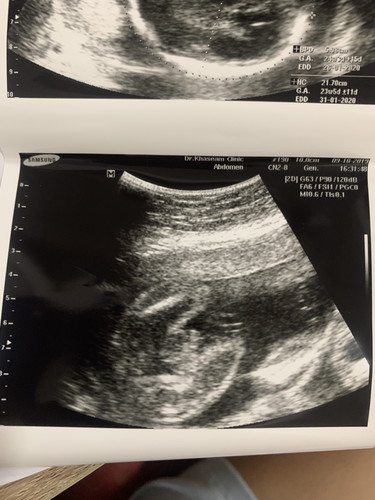

เพศลูก

แม่ๆช่วยดูหน่อยค่ะ ลักษณะนี้เพศอะไรคะ

มองไม่ค่อยชัด แต่เดาว่าชายค่ะ